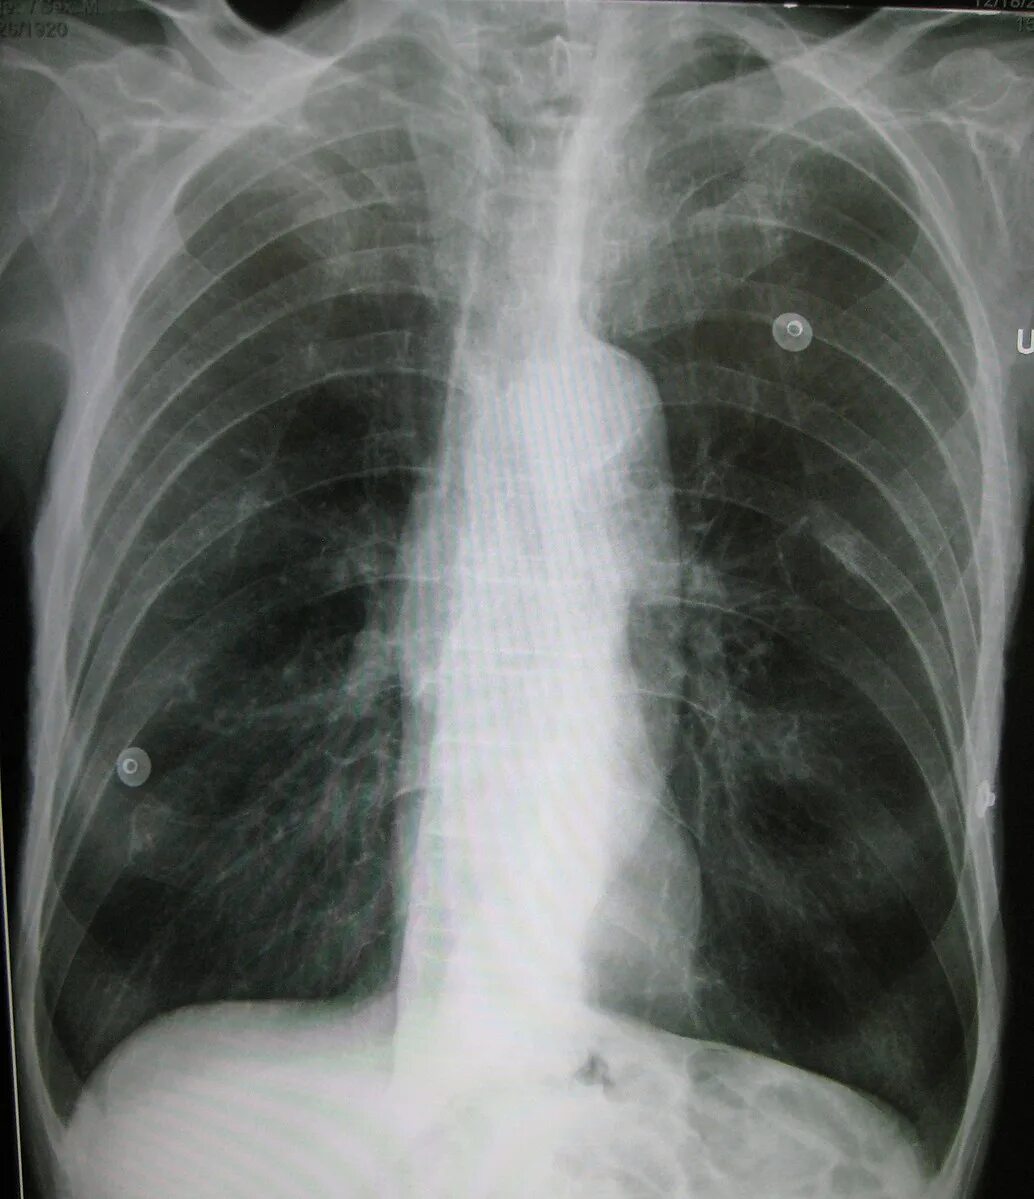

Пятно в легком что это может быть